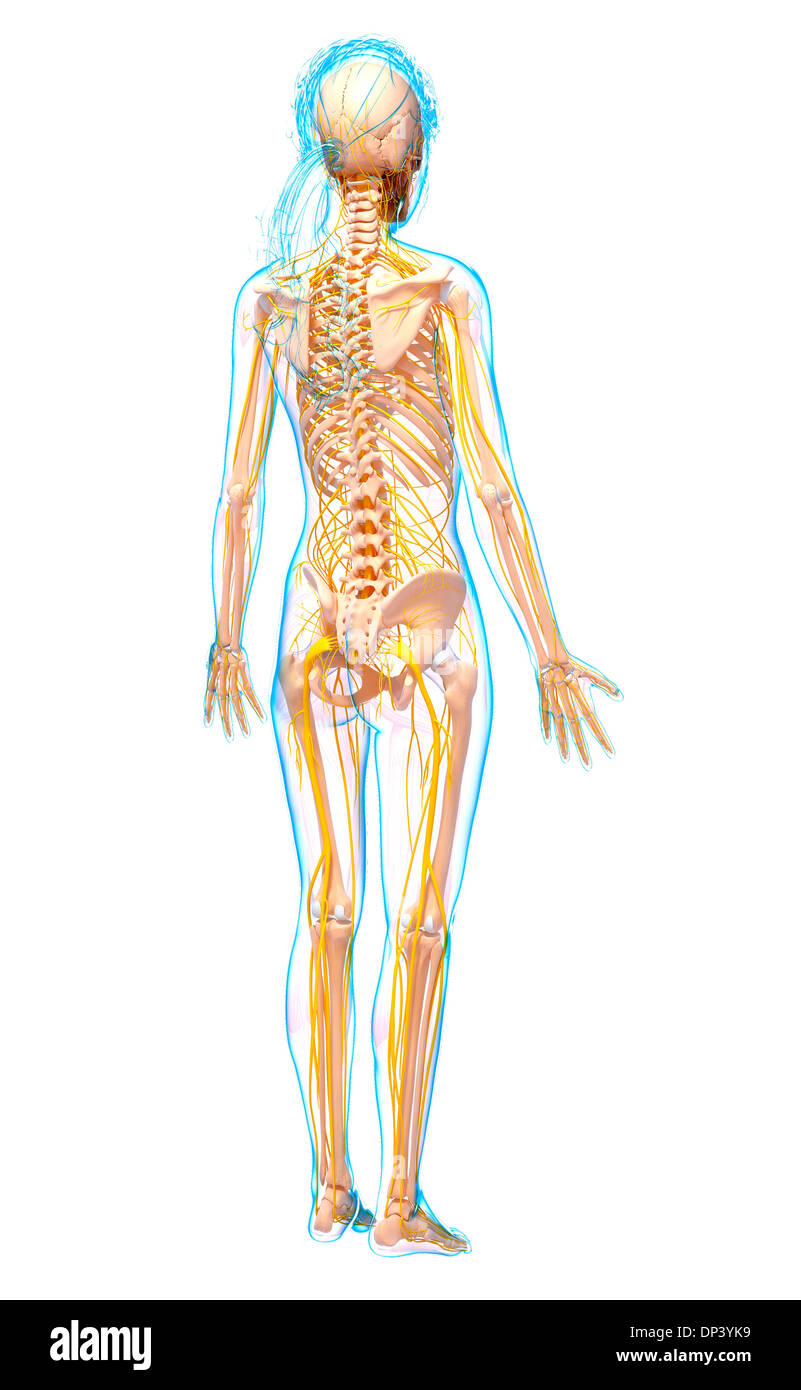

Système nerveux humain, artwork Banque D'Imageshttps://www.alamyimages.fr/image-license-details/?v=1https://www.alamyimages.fr/systeme-nerveux-humain-artwork-image65261837.html

Système nerveux humain, artwork Banque D'Imageshttps://www.alamyimages.fr/image-license-details/?v=1https://www.alamyimages.fr/systeme-nerveux-humain-artwork-image65261837.htmlRFDP4X3W–Système nerveux humain, artwork